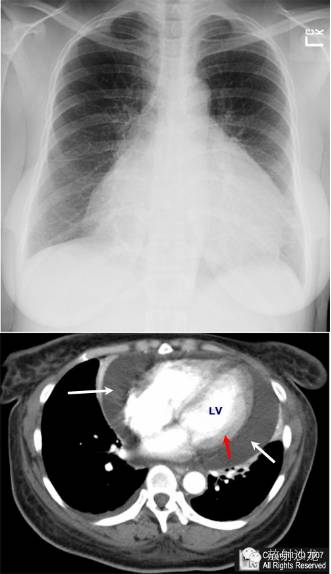

胸部正位片示心影显著增大,鉴别诊断包括心脏肥大及心包积液。心脏水平胸部轴位CT增强扫描示大量心包积液(白箭头)围绕充填对比剂的心脏(LV=左心室),红箭头示心肌。